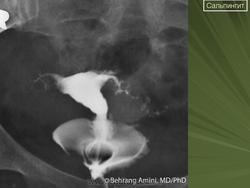

Гидросальпингс.